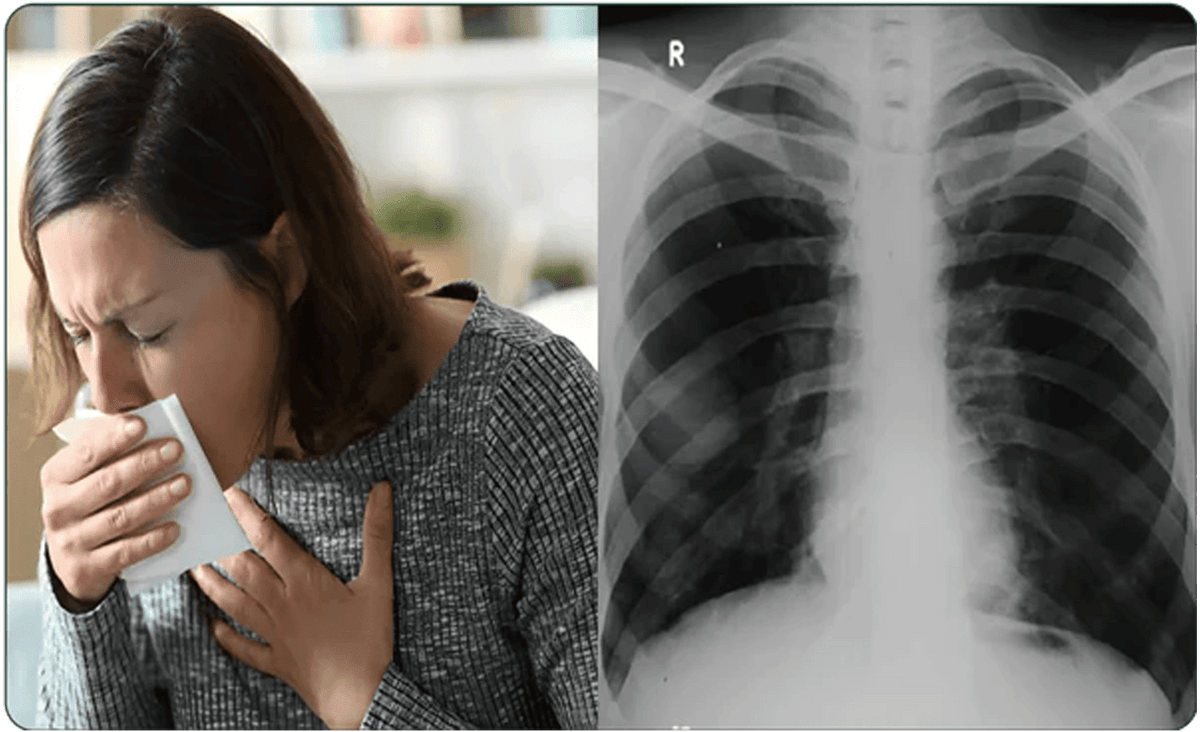

Ondersteun je longgezondheid op natuurlijke wijze

Verlicht hoesten, maak je longen schoon en adem dieper

Ben je het zat om ademhalingsproblemen zonder succes aan te pakken?

Ben je het zat om ademhalingsproblemen zonder succes aan te pakken?

- Ben je vaak kortademig?

- Heb je last van een aanhoudende hoest?

- Ervaar je moeite met ademhalen?

Vergemakkelijkt hoesten en ademen

Ondersteunt schonere, gezondere longen door gifstoffen en verontreinigende stoffen te verwijderen, zodat je dieper en vrijer kunt ademen.

Kalmeert geïrriteerde luchtwegen

Ondersteunt het verwijderen van slijm, maakt het ademen gemakkelijker en verzacht de luchtwegen, wat helpt om hoesten te verminderen.